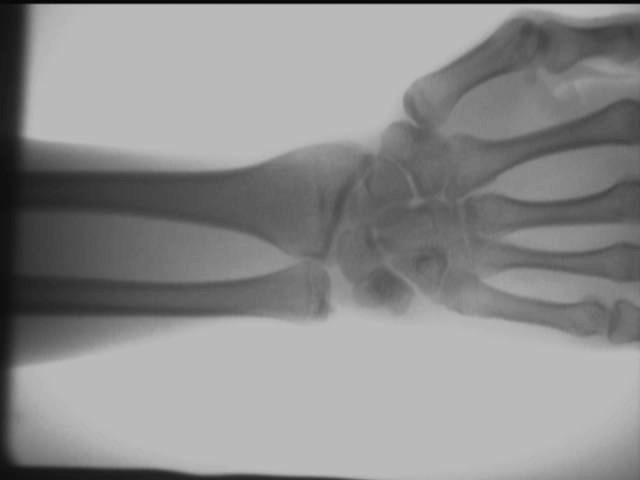

Diagram kesan ujian tapak pengesan sinar-X ortopedik

Kesan sendi buku lali tangan